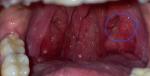

Здравствуйте, замечаю на одной миндалине круглый бугорок. Если нажимать, это место чуть тверже. Сейчас у меня обострение фарингита, заболела. Но, вот этот кружочек (я обвела), он присутствует уже длительно. Скину фото, которое я делала 8 лет назад (вне обострения) и сейчас, чтобы увидеть разницу в увеличении этого шарика.

1) фото без воспаления

2) фото сейчас